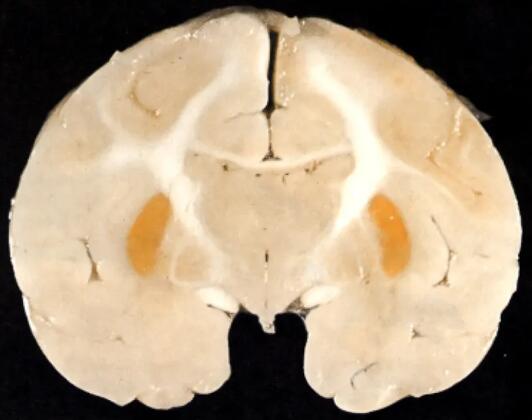

这是因为,胆红素实际上也是一种神经毒素,所以一旦胆红素通过了大脑外的屏障,成功地「入侵」到新生儿的大脑中,就会表现出不同程度的「胆红素诱导的神经功能障碍(bilirubin-induced neurologic dysfunction)」,继而开始对大脑产生很大的伤害。

如果伤害开始了,父母就会开始发现自己的宝宝会有异常的情况了。根据伤害的时间和程度,具体可以分为三个阶段: